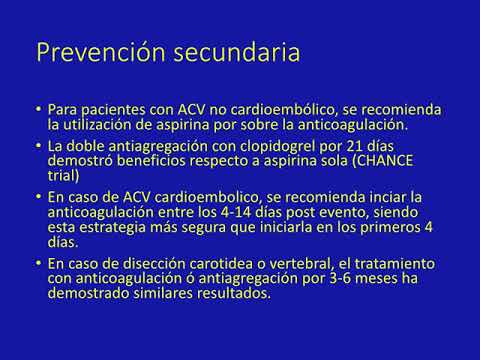

Guía 2018 para el manejo de ACV. Dr. Guido Vannoni. Residencia de Cardiología. Hospital C. Argerich. Buenos Aires